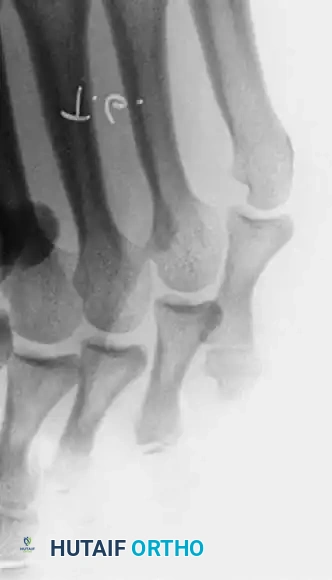

The combined hammer toe and mallet toe deformity, frequently presenting with associated double corns, represents a distinct biomechanical entity in forefoot pathology. It differs fundamentally from the traditional claw toe deformity in that there is minimal to no extension deformity at the metatarsophalangeal (MTP) joint. Instead, the primary deforming forces are concentrated distally, resulting in rigid flexion contractures at both the proximal interphalangeal (PIP) and distal interphalangeal (DIP) joints.

Because of this dual-level contracture, the toe is subjected to abnormal shear and compressive forces within the shoe. Large, prominent hyperkeratotic lesions—double corns—typically develop over the dorsal aspects of both the PIP and DIP joints. The management of these lesions requires a deep understanding of the underlying osseous prominences. In a retrospective review of combined DIP and PIP resection arthroplasties, Oliver et al. reported a 10% recurrence rate at the PIP joint, which they attributed directly to inadequate bone resection during the index procedure.

NONOPERATIVE MANAGEMENT

Keratotic lesions should be managed nonoperatively until the patient has exhausted conservative modalities. Patient education and physician assiduity are essential.